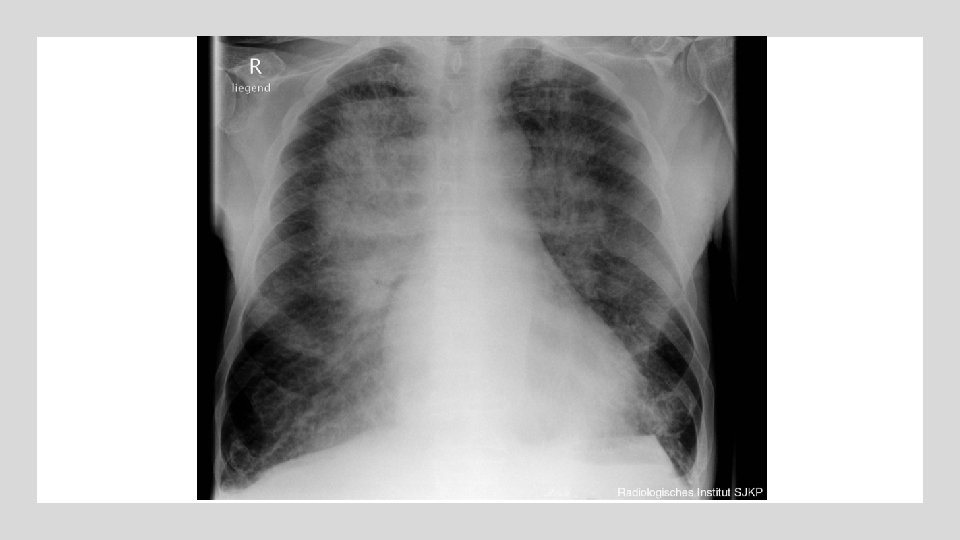

PRUEBAS COMPLEMENTARIAS Pruebas de imagen: Ecografía cardíaca, pulmonar RX tórax § ECG Biomarcadores: Analítica: Ca 125 Creatinina/urea Na/K en sangre y orina Hb (> 10. 5 no se trata) Albúmina Gasometría: - p. H - Hipoxemia/normocapnia NT-pro. BNP